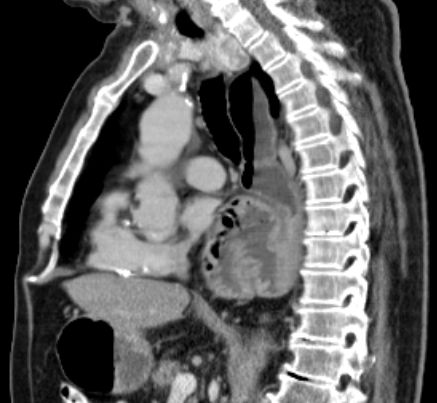

Doppelkarzinom 81-jähriger Patient, der vor 50 Jahren eine 2/3-Resektion des Magens wegen Ulkus hatte.

Vor 4 Jahre Rektum-Karzinom: Radiochemotherapie, Radikaloperation.

Jetzt Einweisung wegen eines Plattenepthelkarzinoms des Magens.

Endoskopie:2 Tumoren. 1.Ösophaguskarzinom mit teilweiser Stenosierung (Plattenepithelkarzinom).

Gesichertes Magenkarzinom ohne Stenosierung (Adenokarzinom).